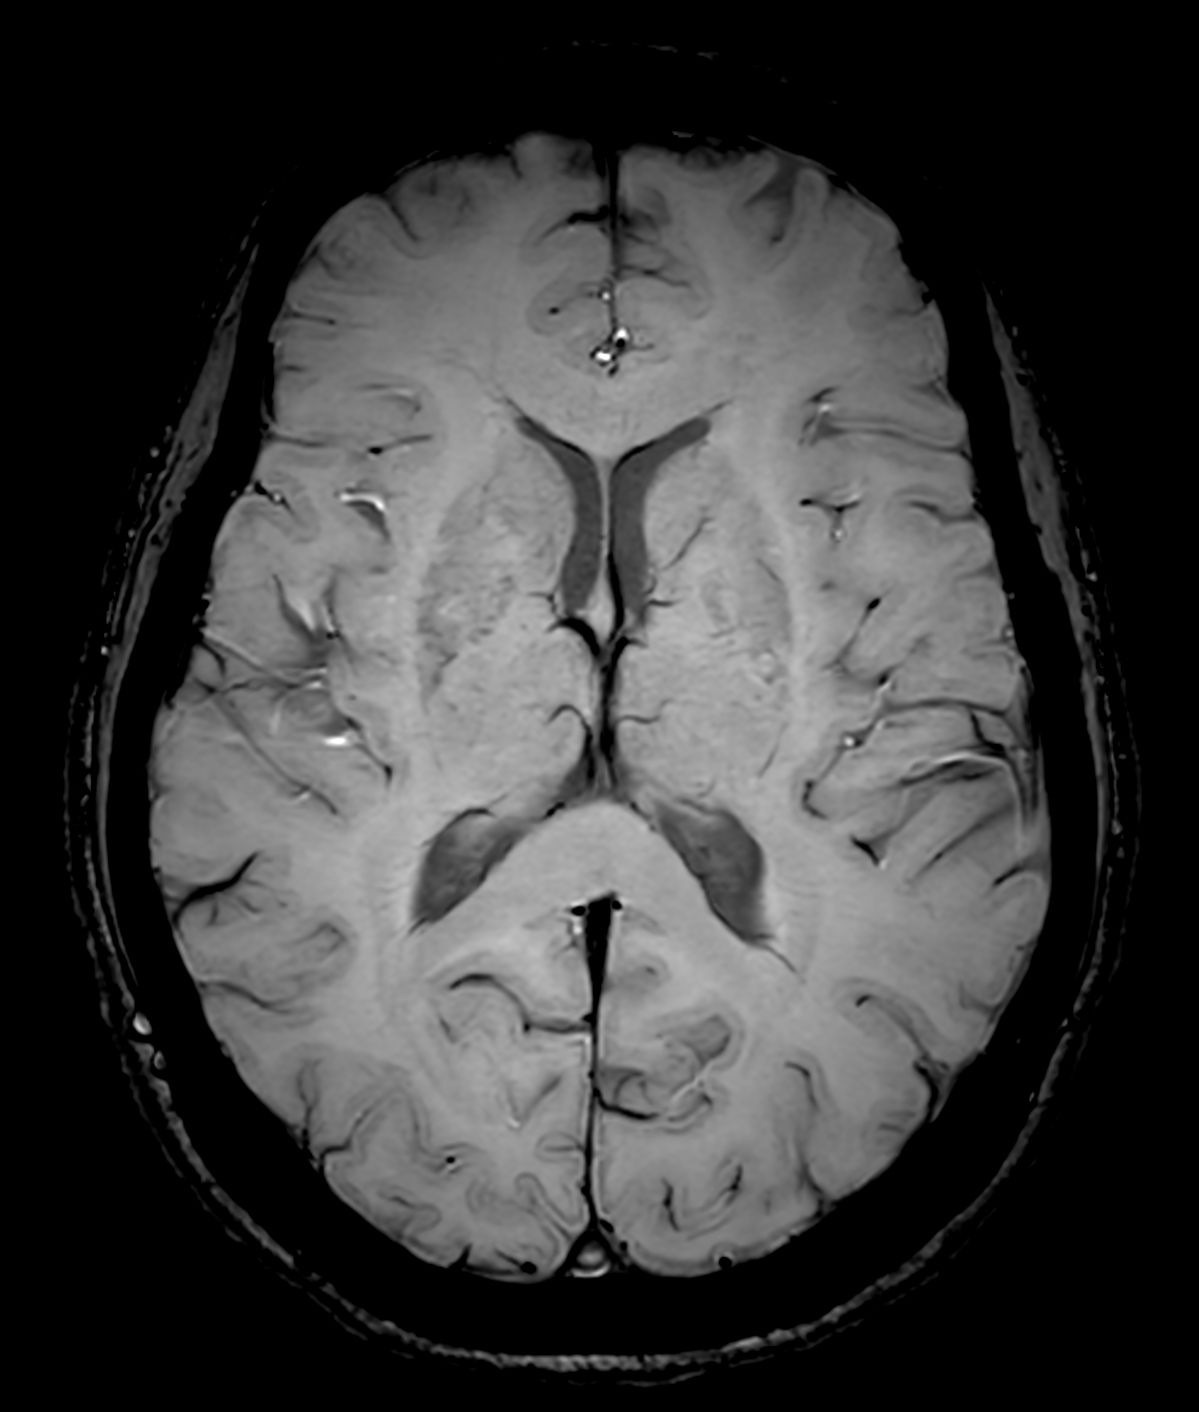

Alzheimer’s Disease Anti-Amyloid Immunotherapies (ARIA) 3.0T

Amyloid clearing medication, such as Aduhelm (Aducanumab) and Leqembi (Lecanemab) have been cleared by the FDA in 2022/2023, to slow down cognitive decline in early-stage Alzheimer’s disease. ASNR-recommendations for AD therapeutic imaging were published in 2022 for eligibility assessment as well as for monitoring for amyloid-related imaging abnormalities. This ExamCard includes ASNR-recommended consensus protocols for imaging of Alzheimer’s Disease Anti-Amyloid Immunotherapies (ARIA). (Cogswell et al., AJNR 2022,43(9)E19-E35;DOI: https://doi.org/10.3174/ajnr.A7586))